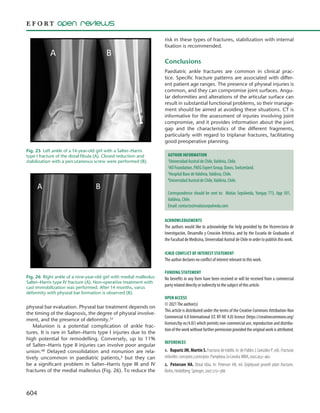

Malunion is a potential complication of ankle frac-

high potential for remodelling. Conversely, up to 11%

of Salter–Harris type II injuries can involve poor angular

union.48 Delayed consolidation and nonunion are rela-

tively uncommon in paediatric patients,3 but they can

be a significant problem in Salter–Harris type III and IV

fractures of the medial malleolus (Fig. 26). To reduce the

risk in these types of fractures, stabilization with internal

fixation is recommended.